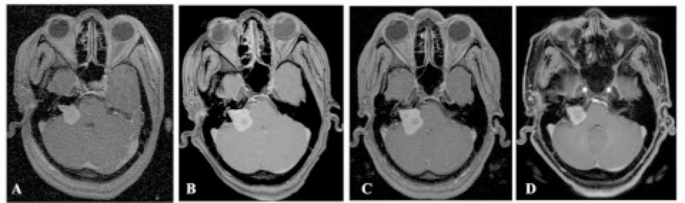

Twenty-seven patients underwent salvage treatment. Nineteen patients (71%) underwent GK re-treatment alone, six patients (22%) underwent surgery alone, and two patients (7%) had surgery then GK re-treatment. The median follow-up duration after salvage treatment was 68 months (4–160 months). The tumor volume according to salvage treatment was; mean 5.4 cc (0.5–15.8 cc) for GK re-treatment alone (Fig. 4), mean 14.9 cc (5–30 cc) for surgery alone, and mean 12.6 cc (12–13.2 cc) for surgery followed by GK re-treatment. The five patients who underwent surgery alone were lost to follow-up. Tumor control was achieved in 19/21 patients (90%). The actuarial tumor control was 94% at 5 years. The tumors shrank in 15 patients (71%), remained stable in 4 patients (19%), and progressed in 2 patients (10%). The two patients with tumor progression are still being followed up.

GK salvage treatment A At the time of treatment; 3.3 cc tumor was treated with 12 Gy to the 50% isodose with 97% cover, B 6 months after treatment 4.8 cc tumor volume (44% TVCp), C 61 months after treatment; 7.2 cc tumor volume (118% TVCf). GK re-treatment was performed to a 7.2 cc tumor that was treated with 12 Gy to the 50% isodose with 97% cover, D 70 months after 2nd GK treatment; 4.6 cc tumor volume (−36% TVC).